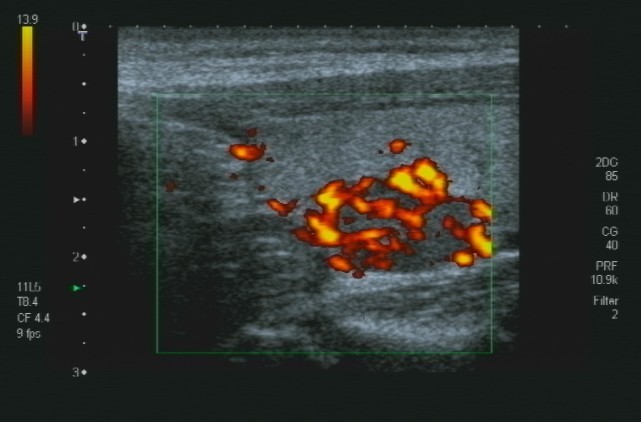

Particolare importanza per lo studio delle patologie focali epatiche, è l'ecografia epatica con mezzo di contrasto o CEUS. La metodica unitlizza ultrasuoni a basso indice meccanico e un ecoamplificatore rapresentato da microbolle iniettate in vena; questo sistema permette in real time la stessa semeitoca TAC o RMN per lo studio delle lesioni focali epatiche.